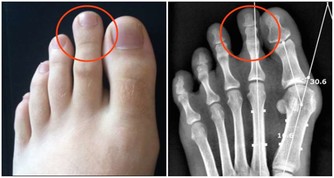

幽門桿菌是寄宿在胃裡的微生物,肉眼看不到,如果有條件去檢查,

在顯微鏡下,就能看到密密麻麻的幽門桿菌,甚是是可怕。